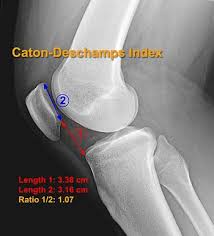

Click on the links to show each structure. Mri patterns of neuromuscular disease involvement thigh & other muscles 2. Injuries of the patellofemoral joint. Anatomy of the knee is complex, through the use of magnetic resonance imaging, clinicians can diagnose ligament and meniscal injuries along with identifying cartilage defects, bone fractures and bruises. Tendons attach the muscles to each other.